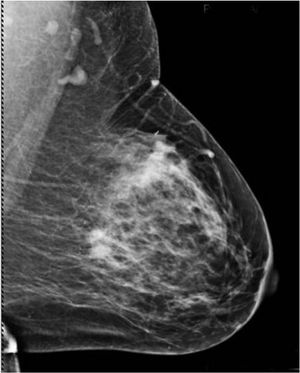

50-year-old patient presented for screening mammogram. Extremely dense breast tissue was noted.